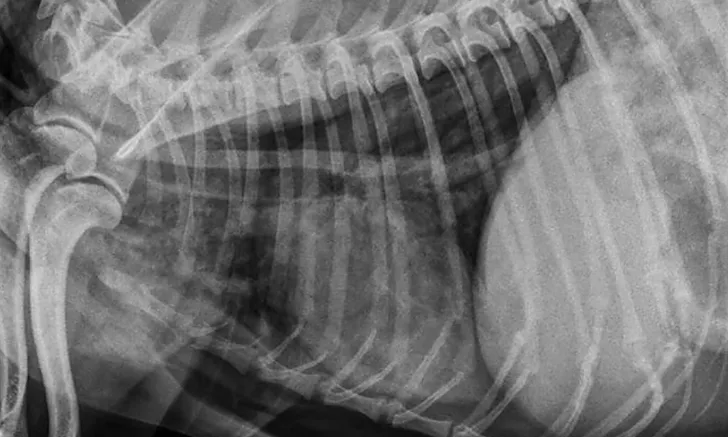

Lateral x-ray showing abnormally detailed views of intrathoracic structures and radiolucency between body wall and skin.

A pneumomediastinum diagnosis is made via thoracic radiography (Figures 1 and 2). Air in the mediastinum outlines the cranial vena cava, dorsal and ventral tracheal walls, esophagus, and aorta. Gas may be present in the retroperitoneal space, cervical fascial planes, and subcutaneous space.2 If an obvious cause of pneumomediastinum is not apparent and the patient is stable, an oropharyngeal examination may be performed with the patient under sedation. Fluoroscopy with iodinated water-soluble contrast or endoscopy can be used to evaluate for esophageal lesions. Airway integrity may be assessed via endoscopy, although small lesions in the trachea may be missed. Advanced imaging (eg, CT) can be helpful in identifying the underlying lesion.